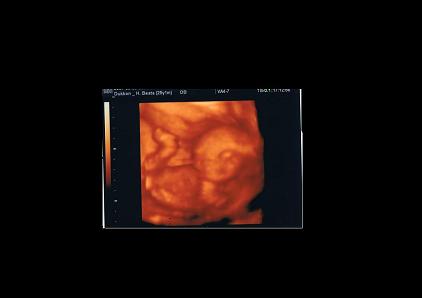

4D-re mi is aug. végén megyünk, ma egyeztettünk időpontot. 30-án, a Balcsi után (oda 22-én megyünk) beqqcskálunk Manóhoz....

Mi a 4D-re a II.kerületbe megyünk.. ott a legolcsóbb (ami meglepett ) és legalább ismerjük is a helyet, mert ott (a kerületben) melózunk....

Ez a hétvégén készült